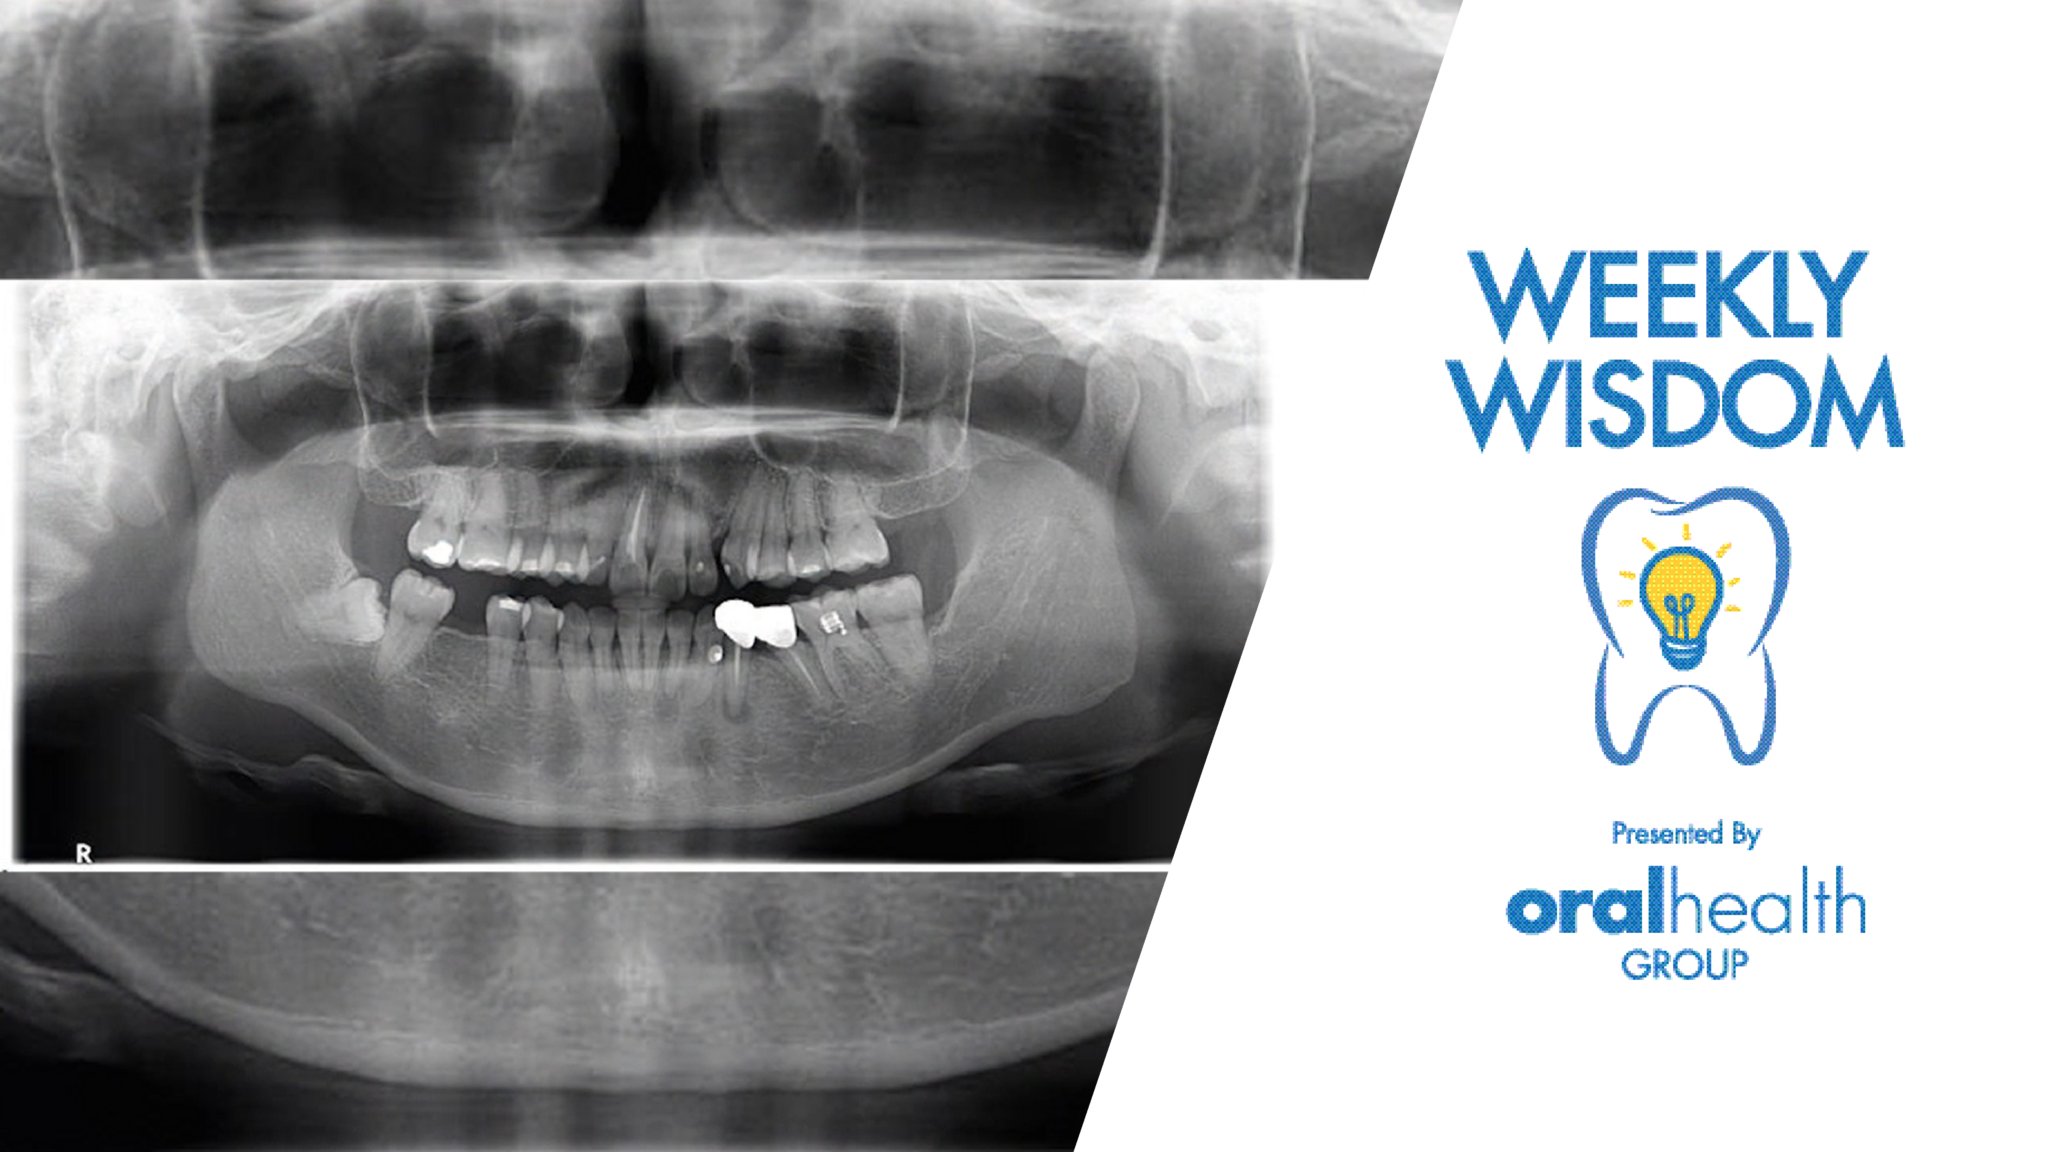

Eh, what’s yer treatment plan doc?

Not going to say a word about this case, the images speak for themselves……….what I’d really like is to have the comments reflect treatment considerations……..if you’re having trouble with Moveable Type and the blog on www.oralhealthjournal.com – kendo@endosolns.com, I’ll post the responses……..it’s the goal of this forum, at least one of them, to create clinical … Read more